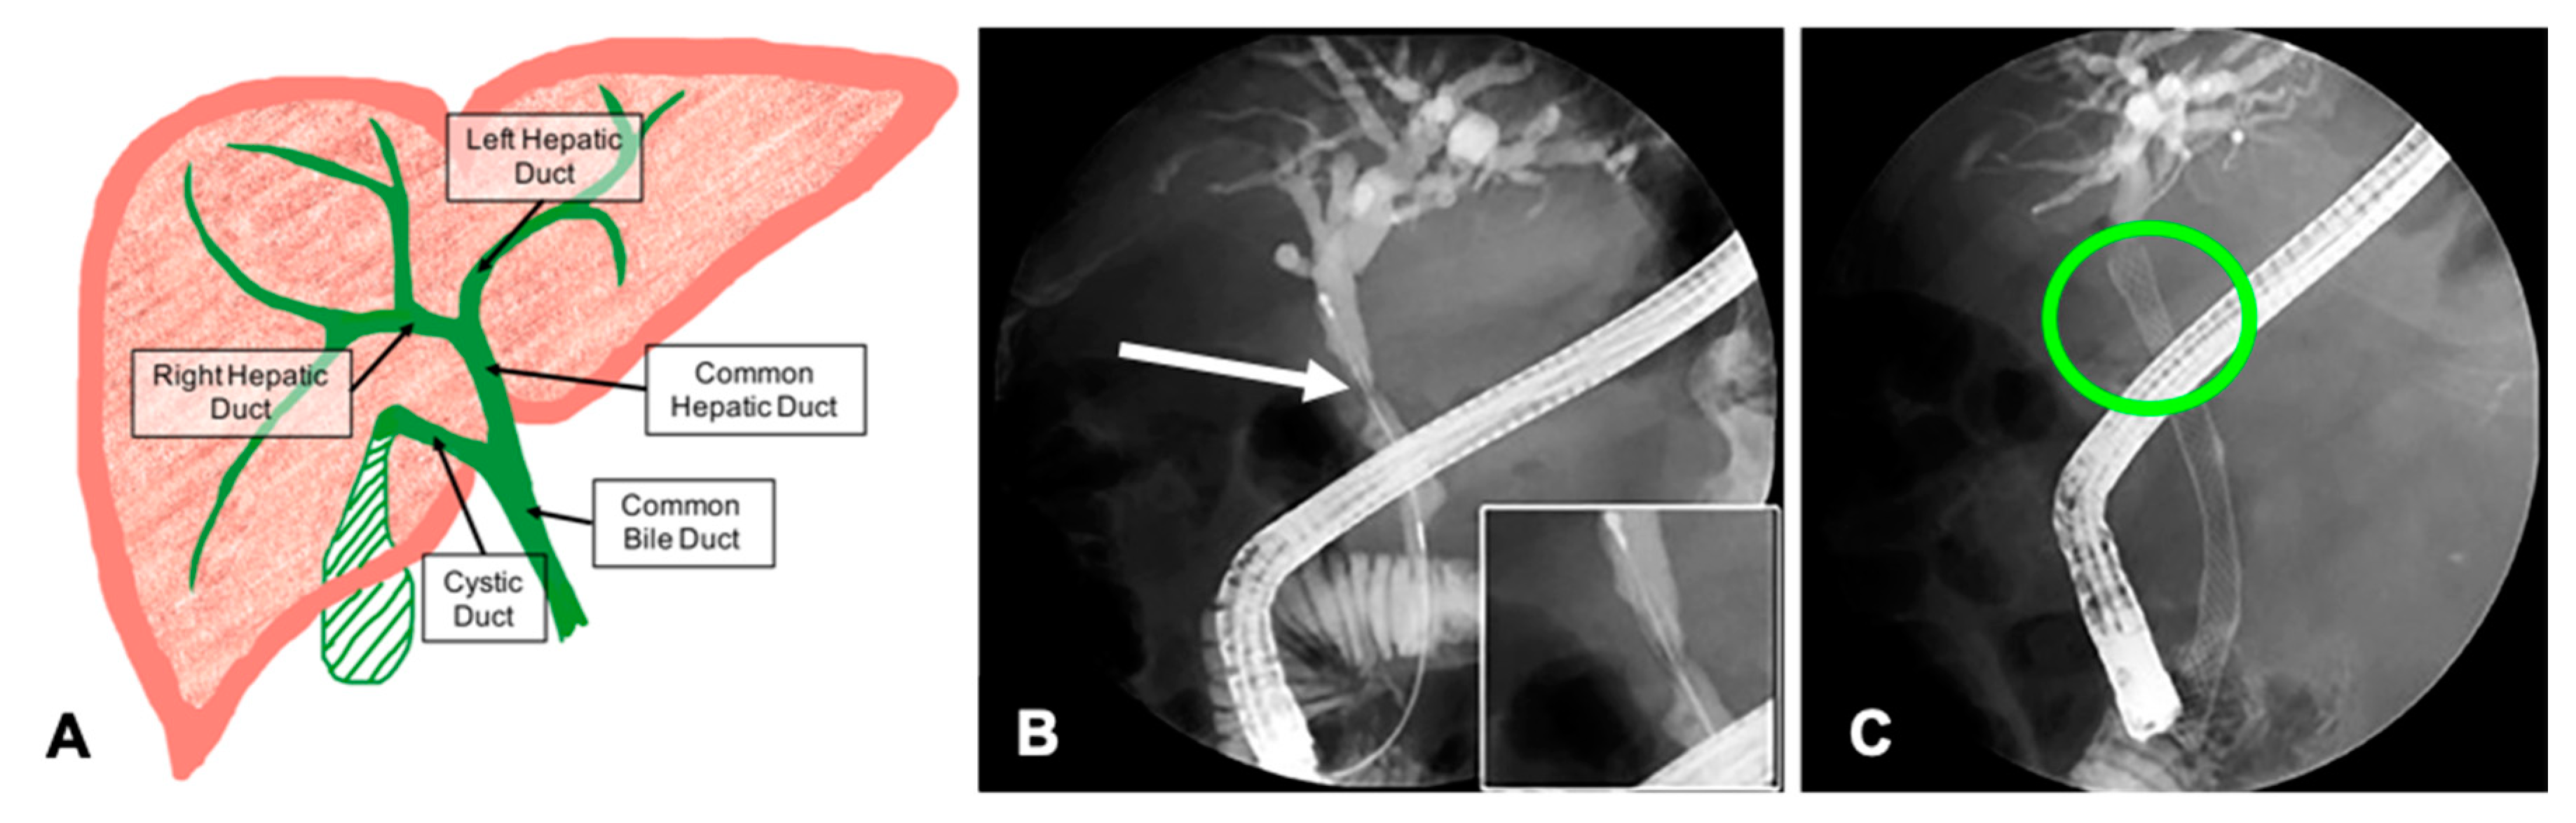

Bile is produced in the liver and drains through the bile ducts into the small intestine where it aids in digestion (Figure 1A). Cholestasis occurs when the bile ducts are inflamed or blocked, and bile is unable to drain out of the liver. Several conditions can cause cholestasis including gallstones, primary sclerosing cholangitis (PSC), and cholangiocarcinoma [,,]. Treatment for acute or chronic cholestasis includes insertion of plastic or self-expanding metal stents (SEMs) into the extrahepatic bile ducts (EHBD) to re-establish bile flow to the intestines (Figure 1B,C).

Figure 1.

Hepatobiliary anatomy and cholestasis caused by a biliary stricture. (A) Anatomically, the extrahepatic ducts begin at the left and right hepatic ducts. They merge to form the common hepatic duct that connects to the gall bladder via the cystic duct. Bile drains into the small intestine through the common bile duct. (B) A significant stricture of the common hepatic duct (CHD) viewed during an endoscopic retrograde cholangiopancreatography (ERCP). The stent catheter has been threaded through the stricture. (C) A SEM stent was deployed to open the stricture and alleviate the cholestasis. (B and C modified with permission from []).